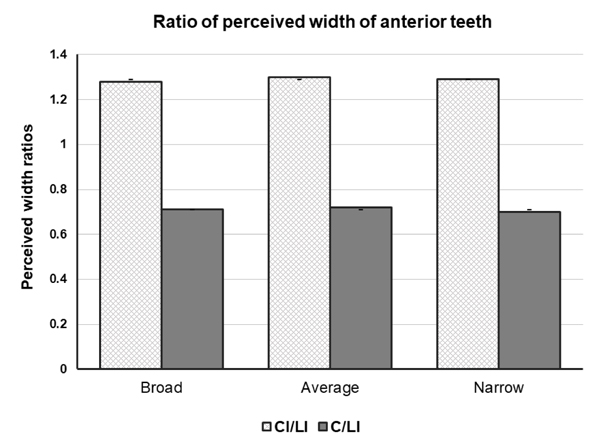

Vincenzo Ronsivalle, Federica Casella, Grazia Fichera, Orazio Bennici, Cristina Conforte and Antonino Lo Giudice